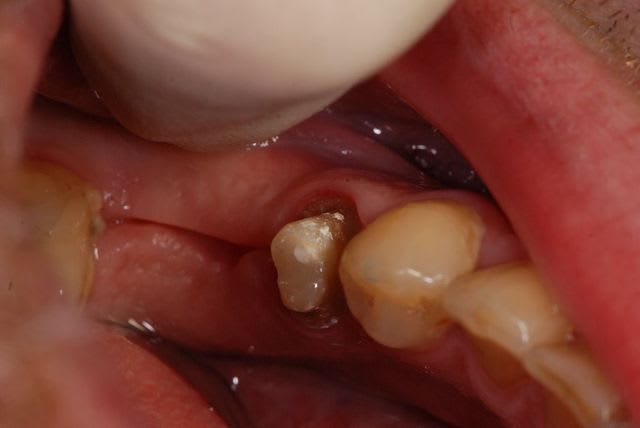

Le mien me sort ça en CCM pour 80 € (12 13). L'autre photo c'est un onlay composite transitoire Adoro sur la 11, 45 €. (Mon capteur photo est sale, je sais)

Il bosse à 5 km du cabinet, petite structure, excellents rapports.

J'en suis satisfait, avec l'expérience je lui trouverai peut être des limites. Franchement, en début de carrière je ne me vois pas bosser avec des labos qui exportent. Pour moi on ne peut pas raler contre le tourisme médical et faire faire sa prothèse à l'étranger. Mais bon quand on est jeune on a des principes...

C'est un cas spécial : une ado de 11 ans, chute de vélo avec fracture coronaire de 11 sur les 3 faces (cf photo le jour de la chute). J'ai tenté 2 composites qui n'ont pas tenu. Là le truc a l'air de tenir, même si j'ai de très gros doutes sur la rétention. Après préparation minimale, c'est collé au SmartCem2 (un automordançant, on tente avec ce qu'on a au cab mais le mieux serait un collage au Variolink).

Dans l'avenir j'aimerais que ça tienne jusqu'à la réalisation d'une CCM/CCC sur dent vivante, à la fin de la croissance.